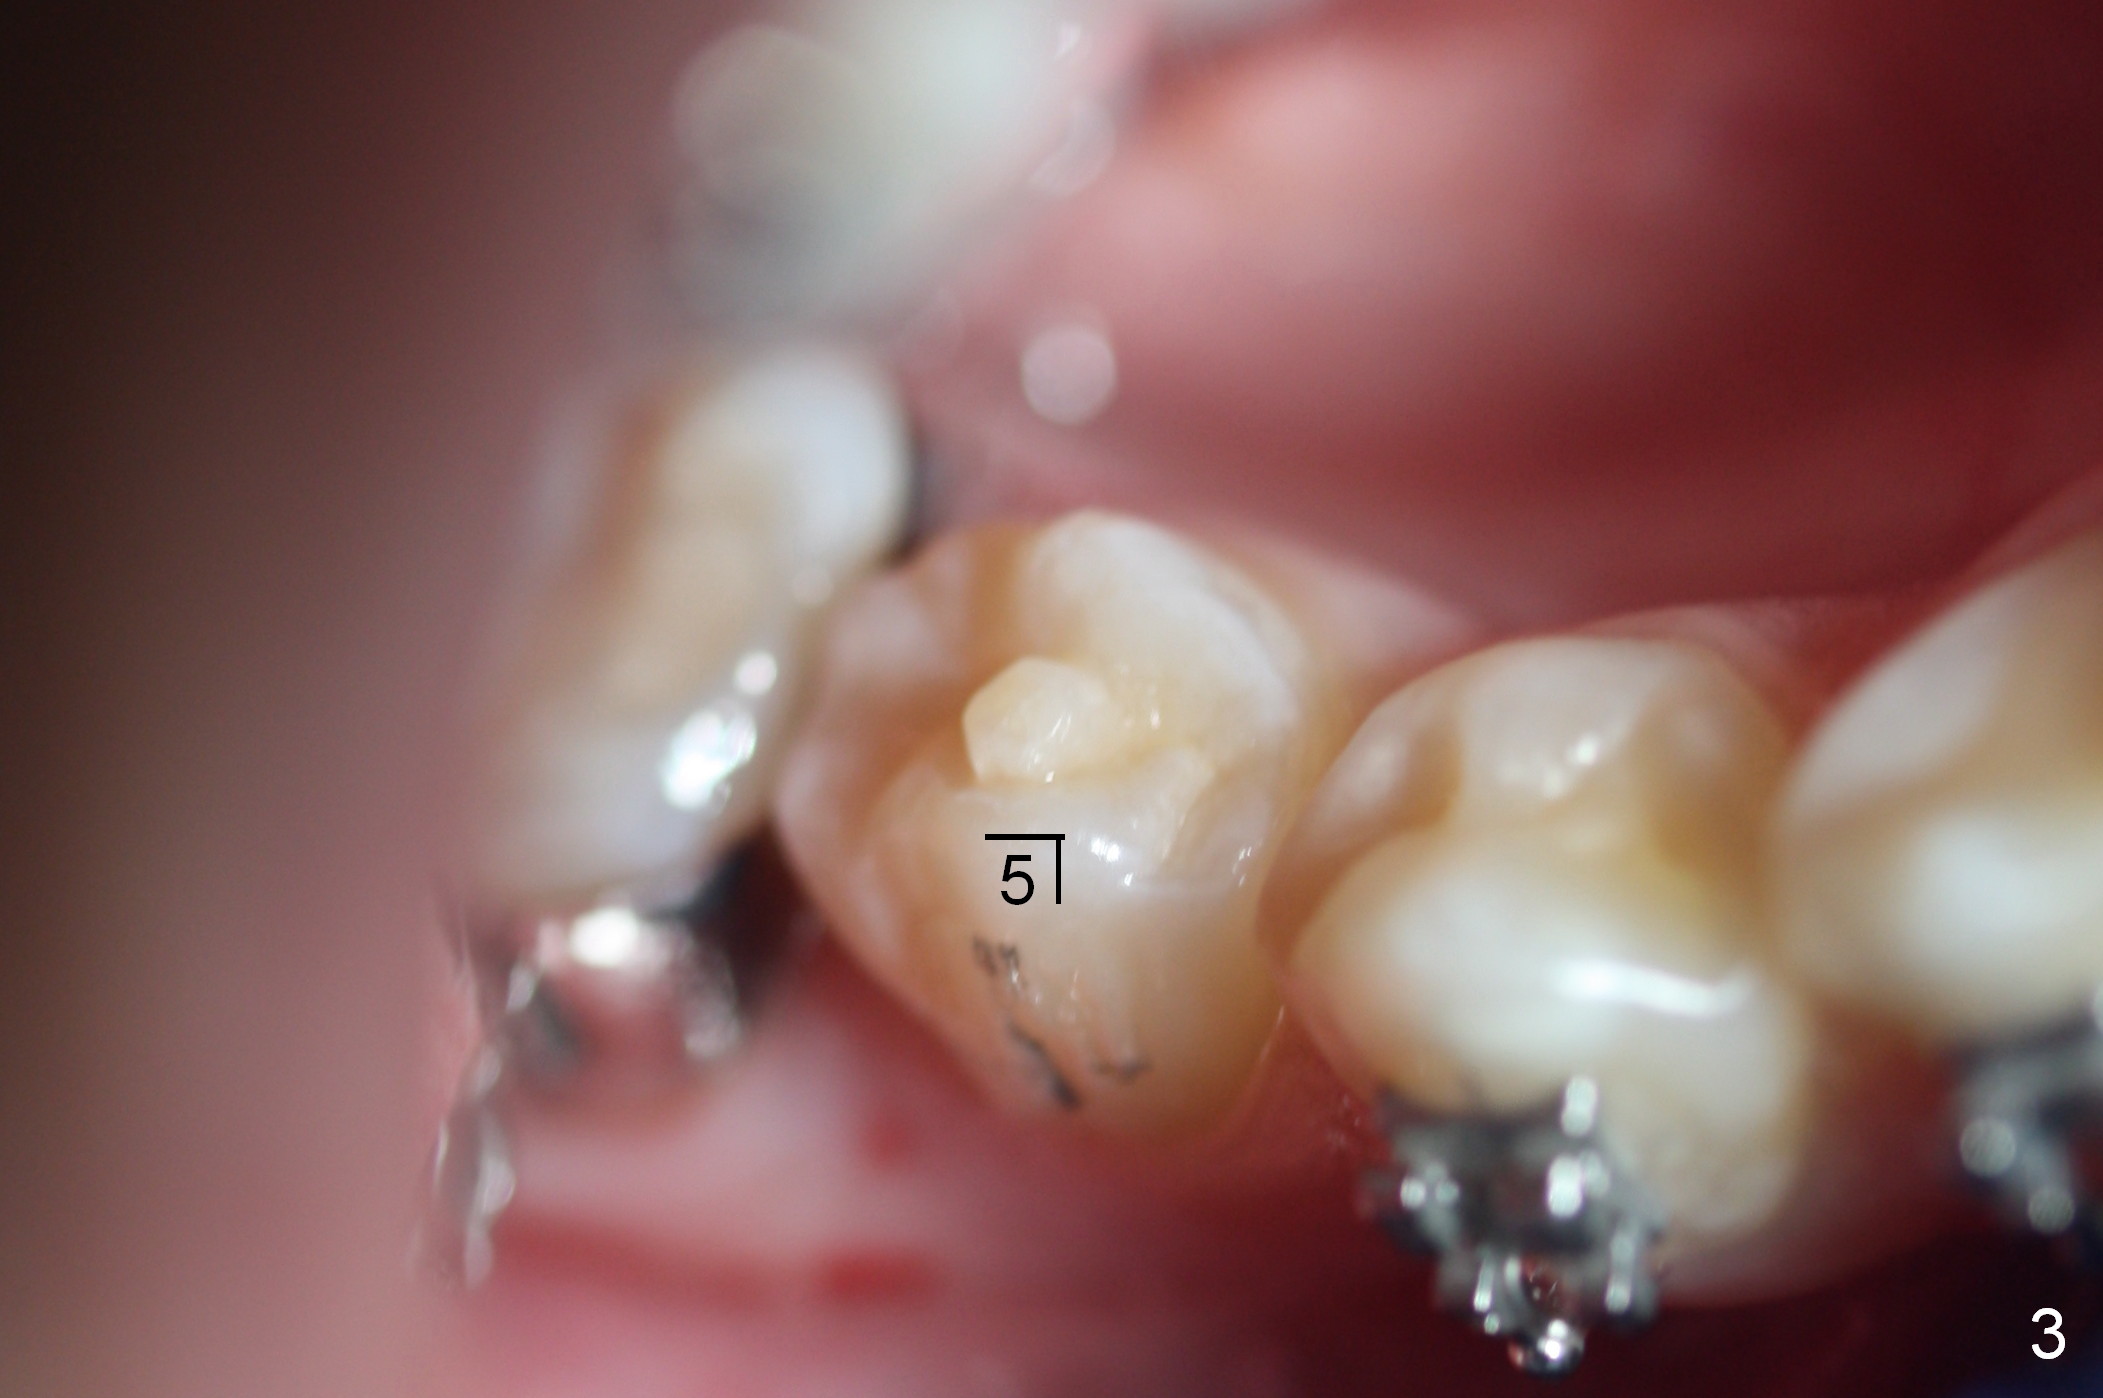

A 15-year-old Spanish female has been in orthodontic treatment for 2 years 3 months (1 2 3). Facial profile is convex (same as preop (Fig.5-8)) with anterior open bite (Fig.1,2). Four bicuspid extraction is considered. Since brackets of the 2nd bicuspids have been lost (Fig.1,2) and there are pathologies associated with the lower ones (Fig.3,4), all of the 2nd bicuspids have been extracted. Plan is to retract the 1st bicuspids, canines and incisors sequentially. How to close the anterior open bite?